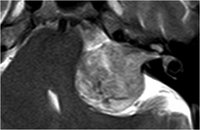

Akustikusneurinom T1 - axial

Akustikusneurinom T2 - axial

Akustikusneurinom T2 - axial - Vergrößerung

Akustikusneurinom T1 mit KM - axial

Akustikusneurinom mit typischem "Eistüten"-Bild.